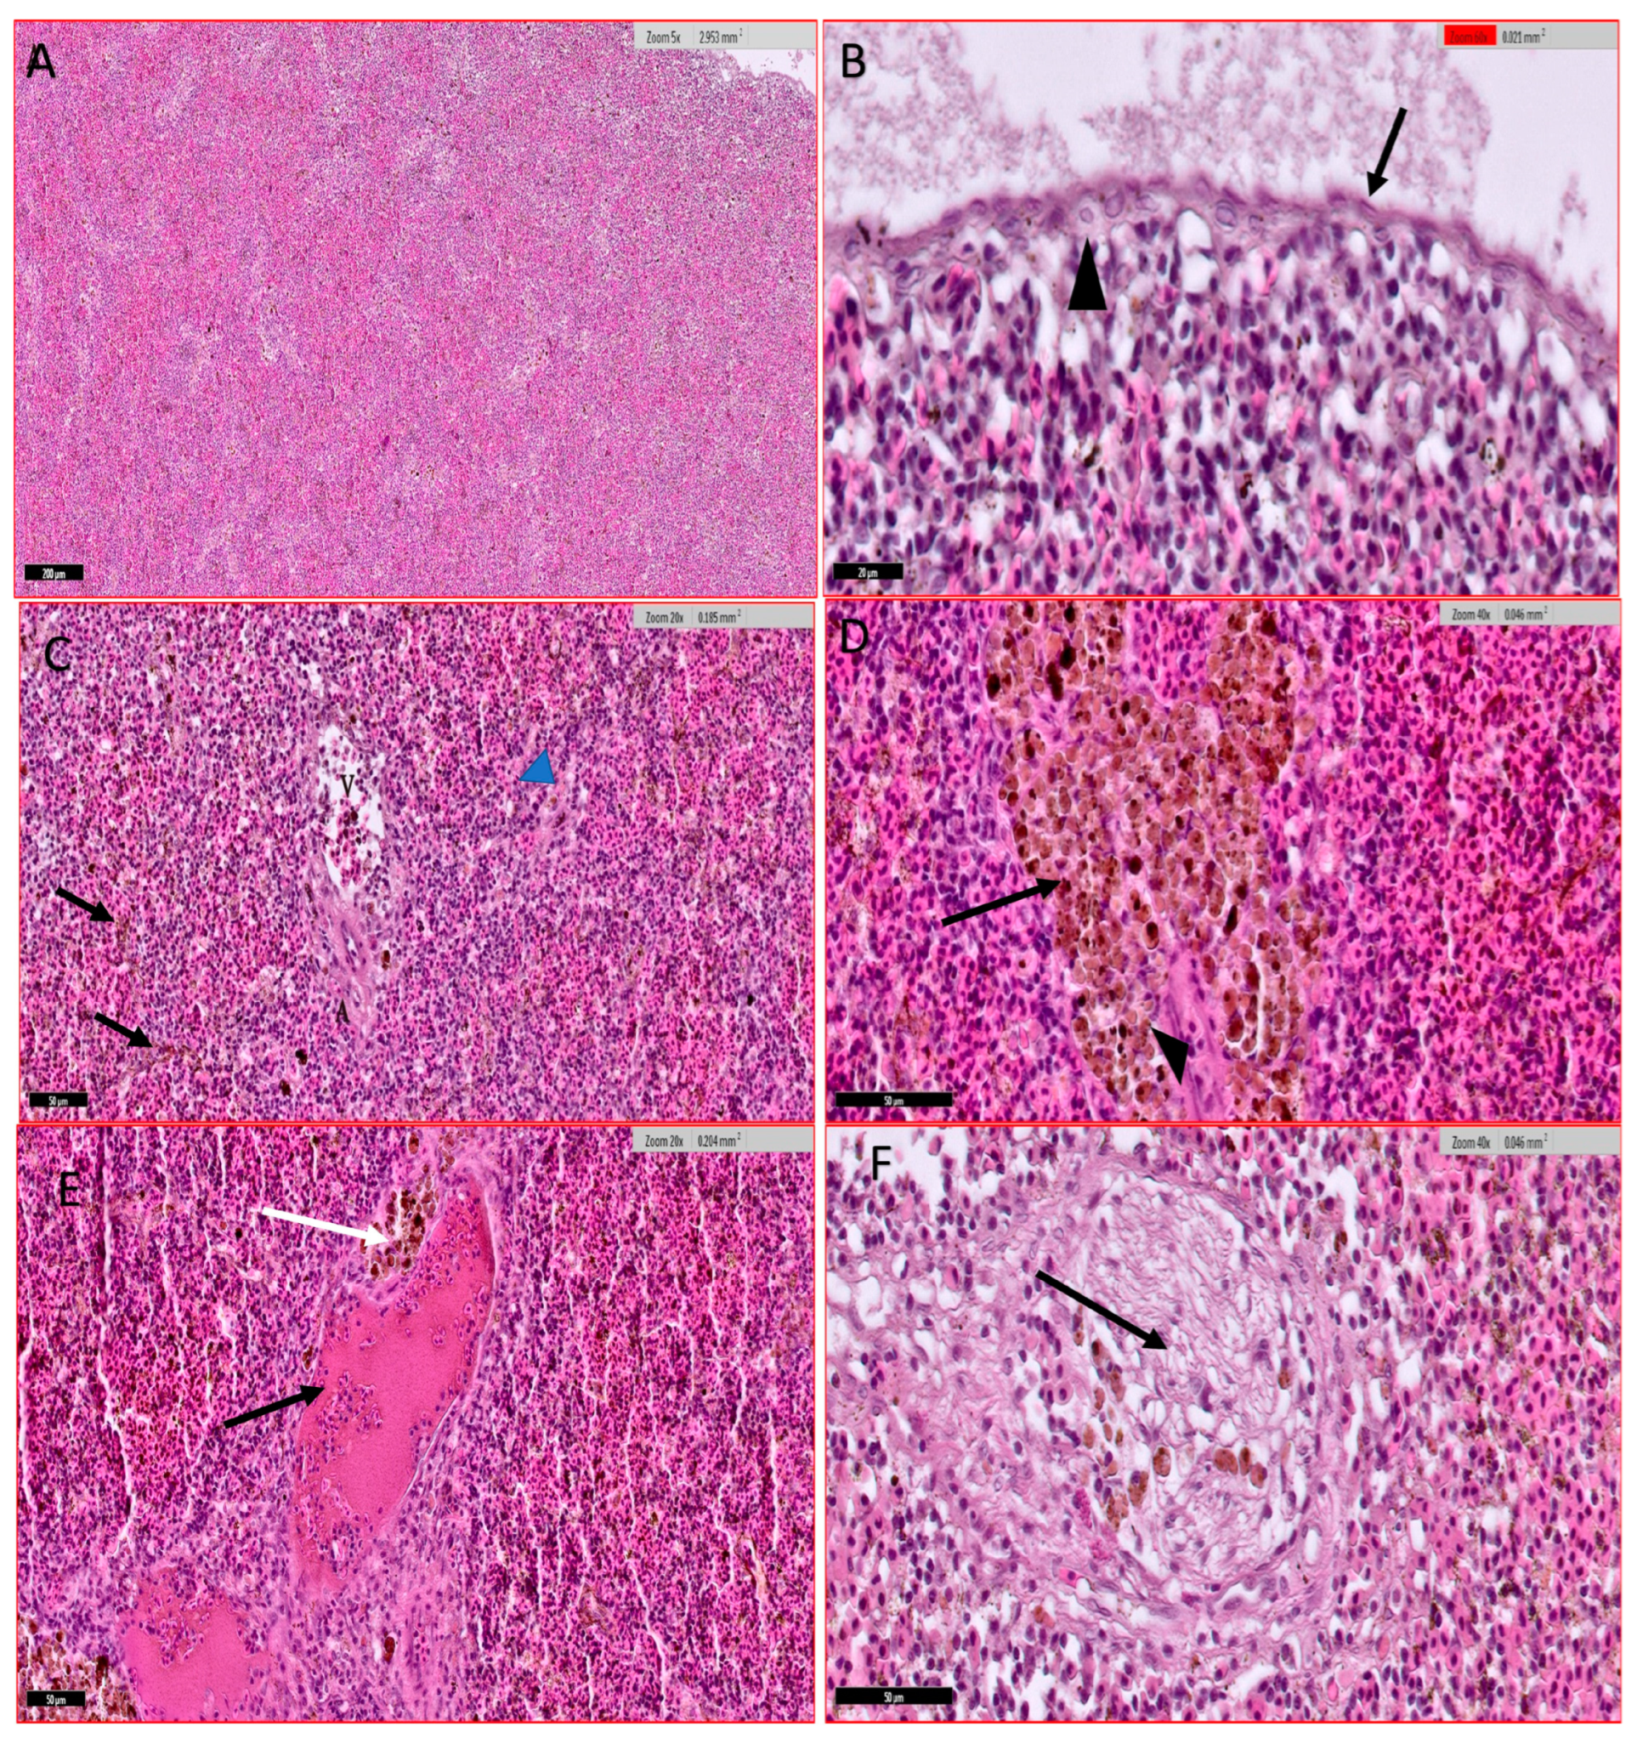

3.4.4. Spleen

3.4.5. Skin